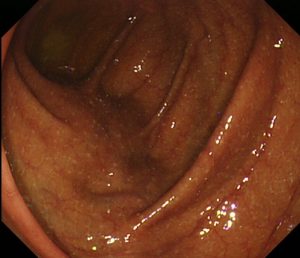

こちらは便秘薬を飲んでいない、きれいな腸粘膜をしています。

こちらと比較して下の大腸粘膜は、

粘膜が蛇の皮のように黒ずんでいます。色素が沈着しているのです。

これを「メラノーシス」と言います。